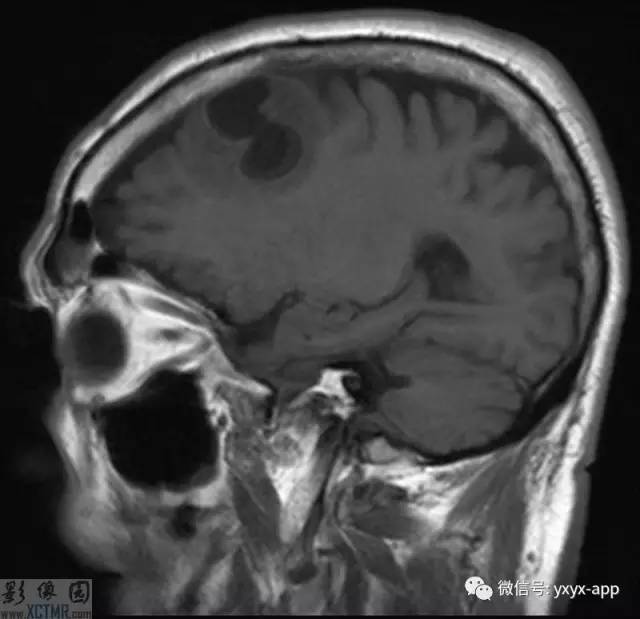

CT:左侧额叶一囊性肿块伴水肿。MRI:轴位T1WI和T2WI显示左侧额叶一囊性肿块伴周围脑实质显著水肿,但无明显占位效应。T1WI增强图显示病变为分叶环形囊状肿块伴周围脑实质水肿,囊壁环形强化,囊内及周围水肿区无强化。

影像学表现取决于感染的位置以及感染的阶段。此病例在胶状水泡阶段,寄生虫的死亡引起明显的炎性反应。影像学表现包括:围绕囊性病变的血管源性水肿;增强后环状增强;T1WI胶状囊性病变周围为低信号;有时可见T1WI头节高信号影。

MRI可以准确地显示各型的发病特点(数目、大小及部位等)。病理演变分期:依据脑囊虫的病理演变过程,将其分为囊泡期、胶样囊泡期、结节期及钙化期,各期由于所含成份的变化,而具有特征性的MRI表现。部分囊泡型及脑炎型脑囊虫病在增强扫描时可呈环形强化,脑炎型脑囊虫病通常为单发环形强化,环一般位于脑皮质内,通常为小环样强化,环壁可厚而光整,但也可厚薄不均匀,环周围常有明显的水肿。这种环形强化病灶与小脓肿环形强化很难区别,需要结合平扫表现和临床。有时环形强化内可见囊虫头节,表现为环形强化内有点状高密度和高信号,使囊虫环形强化的特征性表现,但需要与结核环形强化区别,小囊泡型囊虫病常呈多发环形强化,根据平扫表现,通常容易诊断脑囊虫病。